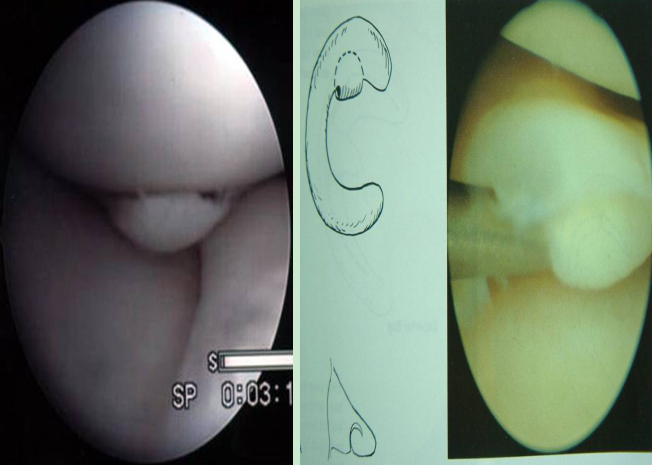

一:盤狀半月板

v原始型(完全型)

v中間型(不完全型)

v嬰兒型(接近正常,但體部鉸寬大)

盤狀半月板完全型

不完全型盤狀半月板